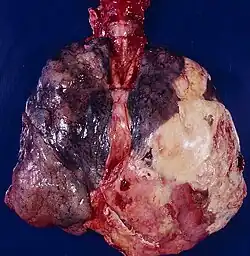

Ранее для лечения применялось хирургическое удаления большинства рёбер с поражённой стороны грудной клетки, что приводило к стойкому коллабированию лёгкого и облитерации инфицированной плевральной полости. Это сопровождалось удалением большой части грудной клетки и выглядело внешне, будто плечо отделяется от туловища (см. рисунок). Сегодня такая операция применяется крайне редко, однако была распространена в период Первой мировой войны[4].